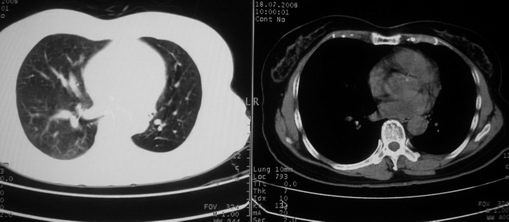

以下是引用李衡钧在2008-7-24 14:24:00的发言:[br]左侧胸廓变小,左肺上叶见大面积致密阴影,其内有空洞及不规则钙化。上纵隔略向左移位,上肺胸膜增厚。左肺门及纵隔淋巴结增大。右肺见散在的致密结节影。[br]印象:继发性肺结核。